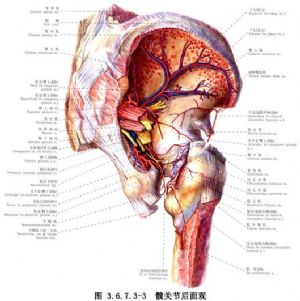

手術相關解剖見下圖(圖3.6.7.3-1~3.6.7.3-4)。